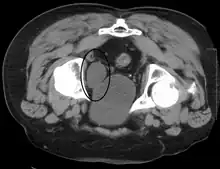

Investigations performed usually include collecting a sample of urine for an inspection for malignant cells under a microscope, called cytology, as well as medical imaging by a CT urogram or ultrasound.[30] If a concerning lesion is seen, a flexible camera may be inserted into the bladder, called cystoscopy, in order to view the lesion and take a biopsy, and a CT scan will be performed of other body parts (a CT scan of the chest, abdomen and pelvis) to look for additional metastatic lesions.[30]

Some forms of medical imaging exist to visualise the bladder. A bladder ultrasound may be conducted to view how much urine is within the bladder, indicating urinary retention. A urinary tract ultrasound, conducted by a more trained operator, may be conducted to view whether there are stones, tumours or sites of obstruction within the bladder and urinary tract. A CT scan may also be ordered.